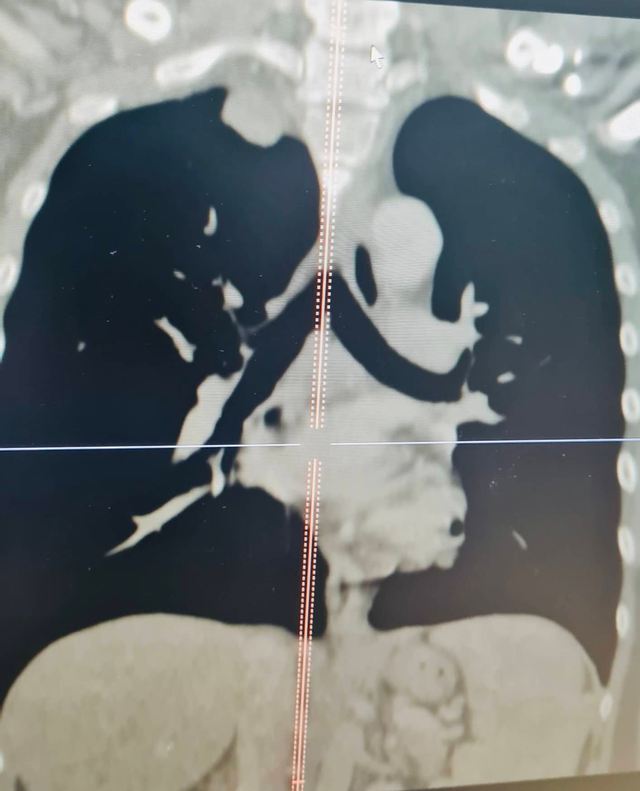

Hình ảnh khối u của bệnh nhân T. trên phim chụp cắt lớp vi tính và cộng hưởng từ

Theo thông tin từ Bệnh viện đa khoa tỉnh Thanh Hóa cho biết, bệnh nhân là anh N.Đ.T. (40 tuổi) vào viện trong tình trạng tức ngực, khó thở kéo dài, đau lưng, vai và cánh tay. Qua chụp cộng hưởng từ và cắt lớp vi tính phát hiện bệnh nhân có khối u từ trong ống sống ngực đã phát triển vào trong lồng ngực với kích thước lớn 3x4cm. Khối u này đã phát triển vào trung thất sau ăn sát hõm đỉnh lồng ngực, đè đẩy vào bó mạch thần kinh cánh tay, đặc biệt là tĩnh mạch dưới đòn trái.